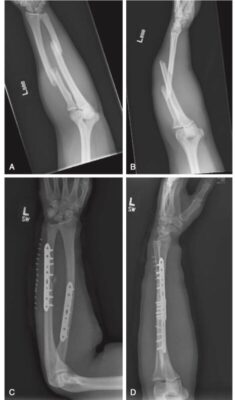

Gãy thân xương quay và xương trụ

Nói chung, gãy ở xương quay và xương trụ được cố định bằng các phương pháp trực tiếp như mổ hở cố định bên trong (ORIF) bằng nẹp vít hoặc các phương pháp gián tiếp như đinh nội tủy. Trường hợp có tổn thương mô mềm đáng kể, có thể đặt dụng cụ cố định ngoài để cố định xương gãy.